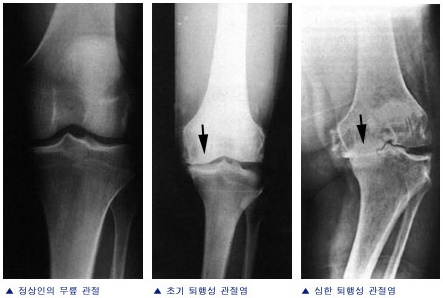

¹«¸­°üÀýÀº ³Ò´Ù¸®Á¤°­°üÀý°ú ³Ò´Ù¸®¹«¸­°üÀý·Î ÀÌ·ç¾îÁø´Ù. ³Ò´Ù¸®Á¤°­°üÀýÀº Á¤°­»À¿Í ³Ò´Ù¸®»ÀÀÇ °üÀý¸éÀÌ Á¢ÃËÇÏ¿© °æÃ¸ ÇüÅÂÀÇ °üÀýÀ» ÀÌ·ç¸ç ¹«¸­ÀÇ Æï°ú ±ÁÈû ¿îµ¿¿¡ °ü¿©ÇÑ´Ù. ¹«¸­°üÀýÀº µ¹¸² ¿îµ¿°ú ¹Ì²ô·¯Áüµµ ÇÔ²² ÀÌ·ç¾îÁö´Â º¹ÀâÇÑ ¿òÁ÷ °üÀý·Î ¹«¸­°üÀýÀÇ ¾ÈÁ¤¼ºÀº ÁÖº¯ÀÇ Àδ볪 ±ÙÀ°µéÀ» ÅëÇØ À¯ÁöµÈ´Ù. ³Ò´Ù¸®¹«¸­°üÀýÀº ¹«¸­»À¿Í ³Ò´Ù¸®»À »çÀÌ¿¡¼­ °üÀýÀ» ÀÌ·ç°í, ¹«¸­ÀÇ Æï, ±ÁÈû ¿îµ¿À» ¿øÈ°ÇÏ°Ô ÇÑ´Ù.´Ù¸®ÀÇ Áß°£ ºÎÀ§¿¡ À§Ä¡ÇÑ´Ù.

¹«¸­Àº ¸ö¿¡¼­ °¡Àå Å« °üÀý Áß ÇϳªÀÌ¸ç °¡Àå ½±°Ô ¼Õ»óµÉ ¼ö ÀÖ´Â °üÀýÀÔ´Ï´Ù. ÀÌ °üÀýÀº ´ëÅð°ñ, °æ°ñ, ±×¸®°í ½½°³°ñ·Î Çü¼ºÀÌ µÇ¾î ÀÖ½À´Ï´Ù. ´ëÅð°ñÀº °æ°ñ À§¿¡¼­ ȸÀü¿îµ¿À» ÇÏ°Ô µÇ°í ½½°³°ñÀº ´ëÅð°ñ ¿øÀ§ºÎ¿Í °üÀýÀ» ÀÌ·ç°Ô µË´Ï´Ù. ¹«¸­ °üÀýÀº ¿©·¯ Àδëµé·Î ¿¬°áµÇ¾î ÀÖÀ¸¸ç ÀÌ´Â ¹«¸­ ¿òÁ÷ÀÓÀ» º¸Á¶ÇÔ°ú µ¿½Ã¿¡ ¿Ü·ÂÀ¸·ÎºÎÅÍ ¹«¸­À» º¸È£ÇØÁÖ´Â ¿ªÇÒÀ» ÇÏ°Ô µË´Ï´Ù. ¶Ç ÇϳªÀÇ ¹«¸­ °üÀýÀÇ Áß¿äÇÑ ±¸Á¶¹°Àº ¼â±â ¸ð¾çÀÇ ¹Ý¿ù»ó ¿¬°ñÀÔ´Ï´Ù. ÀÌ´Â ´ëÅð°ñ°ú °æ°ñ »çÀÌ¿¡ ÀÖÀ¸¸é¼­ ¹«¸­À» º¸È£ÇØÁÖ°í ¹«¸­ ¿òÁ÷ÀÓ¿¡ ´ëÇØ Ãæ°ÝÀ» Èí¼öÇØÁÖ´Â ¿ªÇÒÀ» ÇÏ°Ô µË´Ï´Ù.